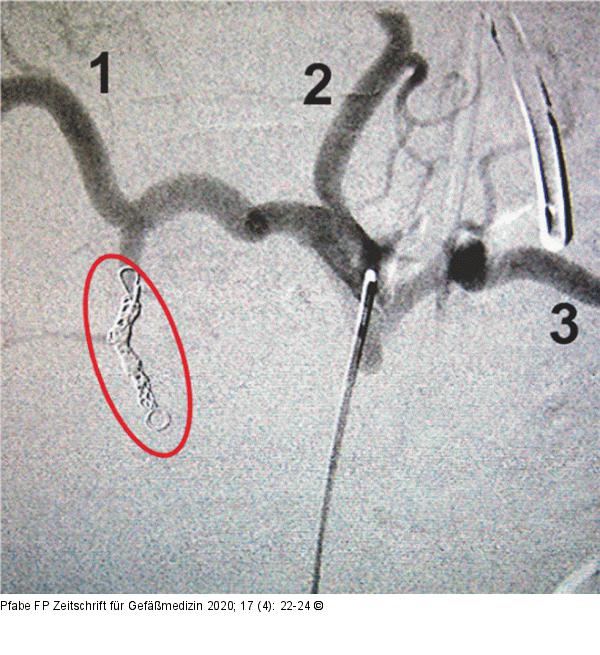

Abbildung 5: Truncus coeliacus Selektive Darstellung des Truncus coeliacus und seiner Hauptäste (1 = A. hepatica, 2 = A. gastrica sinistra, 3 = A. lienalis) in DSA-Technik nach erfolgreicher Embolisation der A. gastroduodenalis. Verschluss der A. gastroduodenalis, keine Kontrastierung distal des embolisierten Gefäßabschnitts (roter Kreis). |

Selektive Darstellung des Truncus coeliacus und seiner Hauptäste (1 = A. hepatica, 2 = A. gastrica sinistra, 3 = A. lienalis) in DSA-Technik nach erfolgreicher Embolisation der A. gastroduodenalis. Verschluss der A. gastroduodenalis, keine Kontrastierung distal des embolisierten Gefäßabschnitts (roter Kreis). |